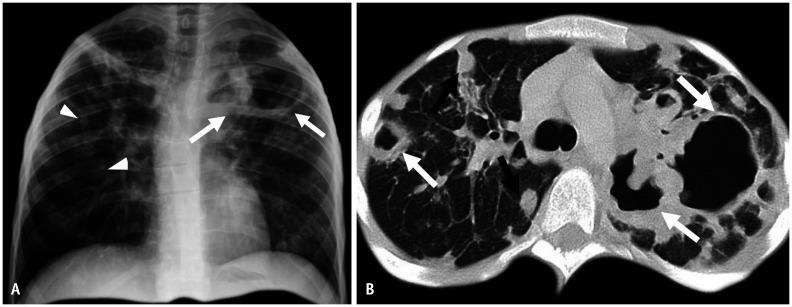

Non-infectious granulomatous lung disease represents a diverse group of disorders characterized by pulmonary opacities associated with granulomatous inflammation, a relatively nonspecific finding commonly encountered by pathologists. Some lesions may present a diagnostic challenge because of nonspecific imaging features; however, recognition of the various imaging manifestations of these disorders in conjunction with patients' clinical history, such as age, symptom onset and duration, immune status, and presence of asthma or cutaneous lesions, is imperative for narrowing the differential diagnosis and determining appropriate management of this rare group of disorders. In this pictorial review, we describe the pathologic findings of various non-infectious granulomatous lung diseases as well as the radiologic features and high-resolution computed tomography imaging features.